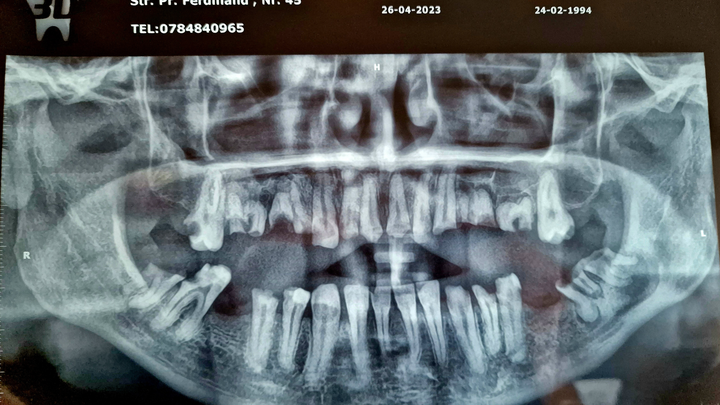

Hello, my name is Cătălin, I'm 31 years old, and I'm from Romania. I'm asking for your help with a problem I've had since childhood, which has started to affect me more and more as the years go by. It’s about a dental problem, and after several check-ups, it was concluded that it’s a hereditary disease, periodontosis, which my father also has. Although I've strictly followed oral hygiene since I was young, I noticed that my teeth and molars began to decay from the root. The cavities advanced to the point where, while eating, pieces of my teeth or molars would break off, even from something as soft as bread. When a molar broke or a tooth became decayed, I would go to the dentist, where they would fill the cavity and send me home. However, over time, I noticed that my entire dentition started to deteriorate from the root, and occasionally, I would find that a molar or tooth would break off at the base of the gum. Regardless of what I ate, I avoided hard foods and was very careful with my diet, knowing that my teeth were very fragile.

Three years ago, four of my upper teeth broke, leaving me with only one. I improvised a plastic mouldable denture (found on Amazon) with which I can still speak, although not very clearly, and I can still smile, albeit with some embarrassment, being the target of jokes from people who don’t understand that anyone can end up in such a situation. In my lower jaw, I have five teeth and only one molar left, which barely helps me to eat. The rest of my teeth are destroyed, with the teeth and molars broken at the base. Last year, in a moment of vulnerability, I inquired with several clinics about the cost of restoring my teeth, both in Romania and in Turkey, where I heard it is cheaper and faster. The cheapest option I received was from a clinic in Turkey, based on a 3D scan of my teeth. In total, the cost would be £13,000, including 12 implants, 2 bone grafts, and the temporary denture, with the permanent denture to be fitted later. They informed me that I need 6 implants on the upper jaw and 6 on the lower jaw because, due to the disease I suffer from, fewer than 6 implants per arch wouldn’t provide enough strength, as the bone is quite weak.